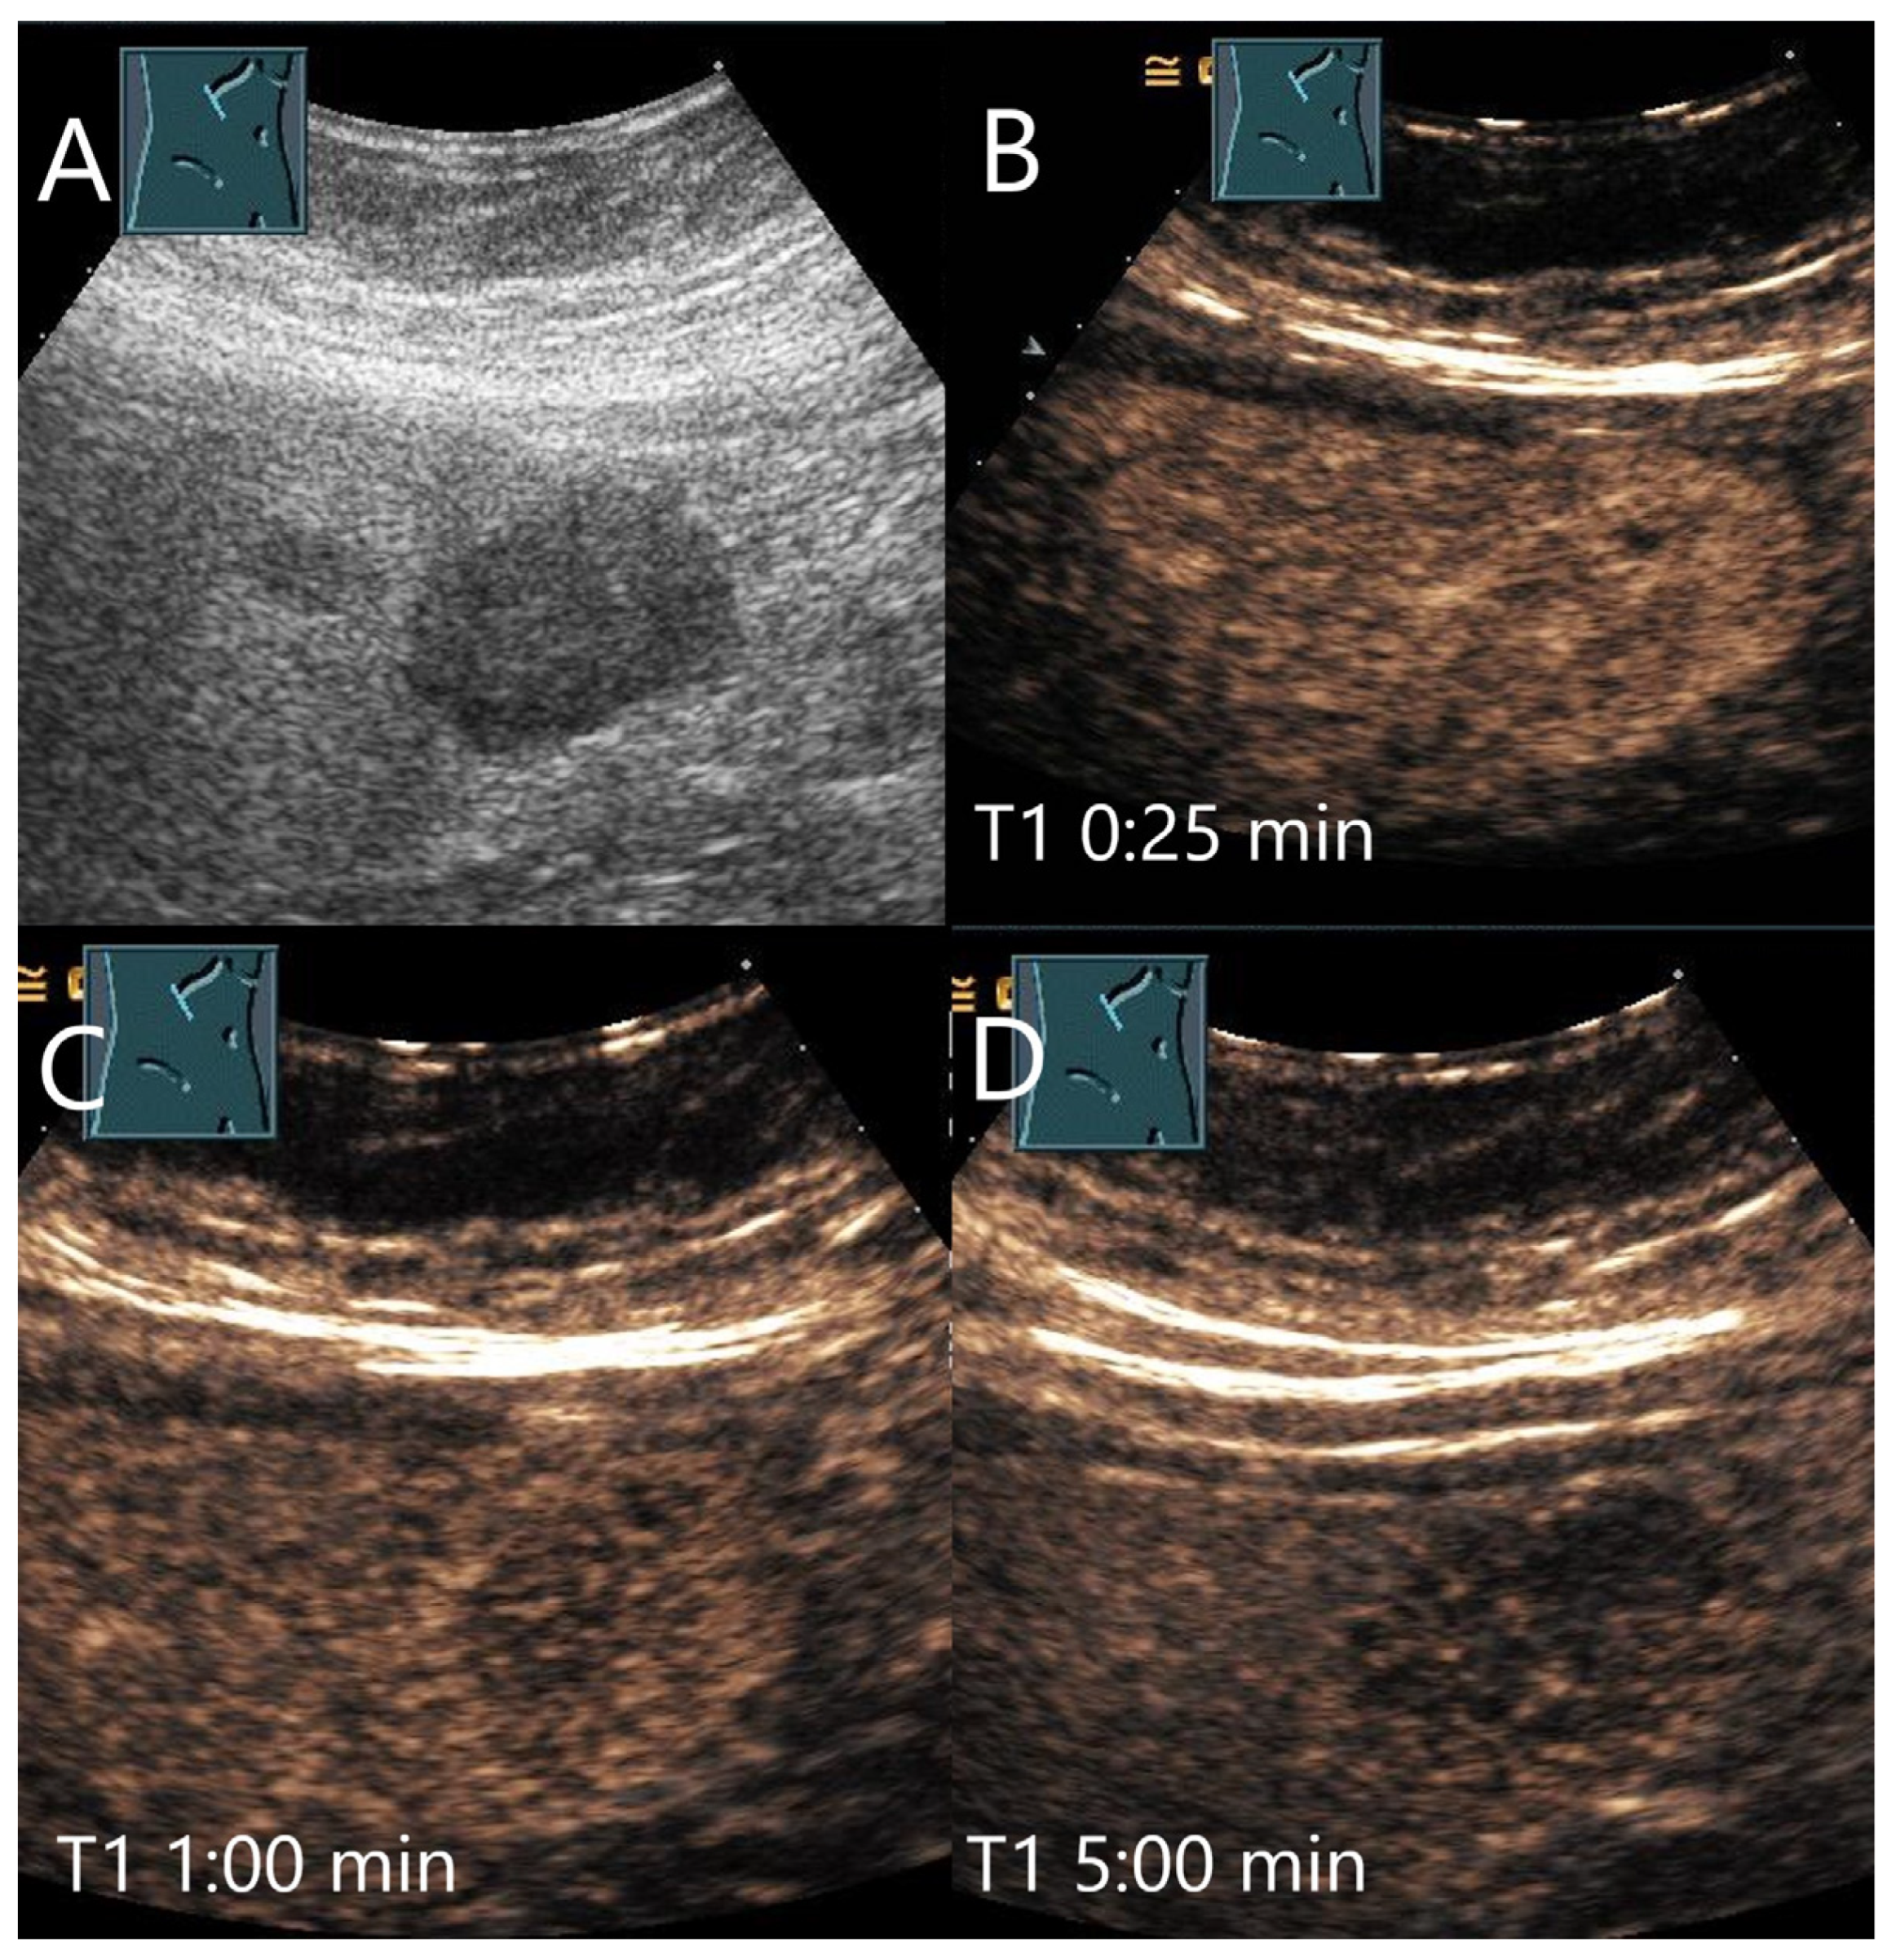

Figure 19.

Peliosis hepatis. Female patient. Hypoechoic lesion of 40 × 28 mm in a mildly steatotic liver (A). The CEUS shows arterial hyperenhancement after 25 s (B) with mild predominantly central hypoenhancement after 1 min (C) and 5 min (D). Histological confirmation was performed by US-guided biopsy. The adjacent small hypoechoic lesion (A) is isoenhanced in the CEUS in all phases.